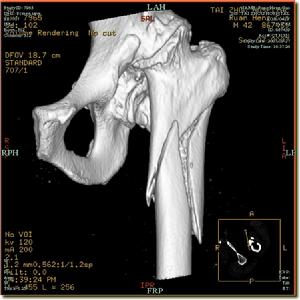

在有條件時可套用CT或MRI檢查便可明確診斷。

2.股骨頭 新生兒的股骨頭為畸形,表面有光滑的軟骨面,而後由於脫位於髖臼外,股骨頭的形狀可逐步改變,頭可變大或變小,呈尖錐形或葺形,股骨頭受壓處往往出現部分股骨頭扁平。股骨頭骨骺出現遲緩。有時套用強大暴力手術復位,由於髖臼與股骨頭不相適應,對股骨頭的壓力過大,可造成股骨頭無菌性壞死。

3.股骨頸 由於髖關節脫位,股骨頸一般變短而粗,是肢體縮短的一個原因。股骨頸前傾角變大,據Caffey報導正常新生兒前傾角為25°,以後逐步減少至5°~15°之間,當股骨頭外移後,由於正常肌力作用,向股骨頭向前鏇轉,前傾角因而增大,一般在60°~90°之間。如果能早期復位,前傾角多能逐步自行糾正。尤其在1歲以內得到復位者幾乎都能恢復正常。

4.骨盆和脊柱 脫位一側的骨盆往往伴有發育不良情況,髂翼較斜,坐骨結節較分開。在兩側脫位時,以上病變存在外,骨盆向前傾斜而使腰前突弧度增加,有時可以出現側彎。

2.關節囊 正常的髖關節囊是一層纖維組織0.5~1.0mm厚薄。自從股骨頭脫離髖臼向外向上移位,小孩負重後,關節囊受到牽拉而增長增厚有時可大2~3mm之多,長期牽拉使關節囊與髖臼上方髂翼粘連,加上圓韌帶、盤狀軟骨與關節囊之間粘連,形成整整一片結締組織,阻礙股骨頭進入髖臼。關節囊在後期呈葫蘆形,有狹窄的頸部,股骨頭本身就不能通過。髂腰肌腱經過關節囊前面,有時在很早期出現一個切跡,阻礙股骨頭復位。關節囊附著在股骨頭以下而不是附著大小粗隆之間。